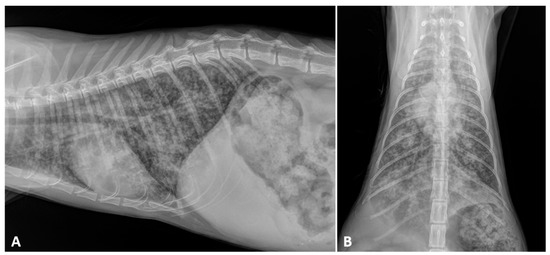

2.2. Radiographic Findings

- Crisi, P.E.; Aste, G.; Traversa, D.; Di Cesare, A.; Febo, E.; Vignoli, M.; Santori, D.; Luciani, A.; Boari, A. Single and mixed feline lungworm infections: Clinical, radiographic and therapeutic features of 26 cases (2013-2015). J. Feline Med. Surg. 2017, 19, 1017–1029. [Google Scholar] [CrossRef] [PubMed]

- Febo, E.; Crisi, P.E.; Traversa, D.; Luciani, A.; Di Tommaso, M.; Pantaleo, S.; Santori, D.; Di Cesare, A.; Boari, A.; Terragni, R.; et al. Comparison of clinical and imaging findings in cats with single and mixed lungworm infection. J. Feline Med. Surg. 2019, 21, 581–589. [Google Scholar] [CrossRef]

- Genchi, M.; Ferrari, N.; Fonti, P.; De Francesco, I.; Piazza, C.; Viglietti, A. Relation between Aelurostrongylus abstrusus larvae excretion, respiratory and radiographic signs in naturally infected cats. Vet. Parasitol. 2014, 206, 182–187. [Google Scholar] [CrossRef]

- Lacava, G.; Zini, E.; Marchesotti, F.; Domenech, O.; Romano, F.; Manzocchi, S.; Venco, L.; Auriemma, E. Computed tomography, radiology and echocardiography in cats naturally infected with Aelurostrongylus abstrusus. J. Feline Med. Surg. 2017, 19, 446–453. [Google Scholar] [CrossRef]

- Dennler, M.; Bass, D.A.; Gutierrez-Crespo, B.; Schnyder, M.; Guscetti, F.; Di Cesare, A.; Deplazes, P.; Kircher, P.R.; Glaus, T.M. Thoracic computed tomography, angiographic computed tomography, and pathology findings in six cats experimentally infected with aelurostrongylus abstrusus. Vet. Radiol. Ultrasound 2013, 54, 459–469. [Google Scholar] [CrossRef]